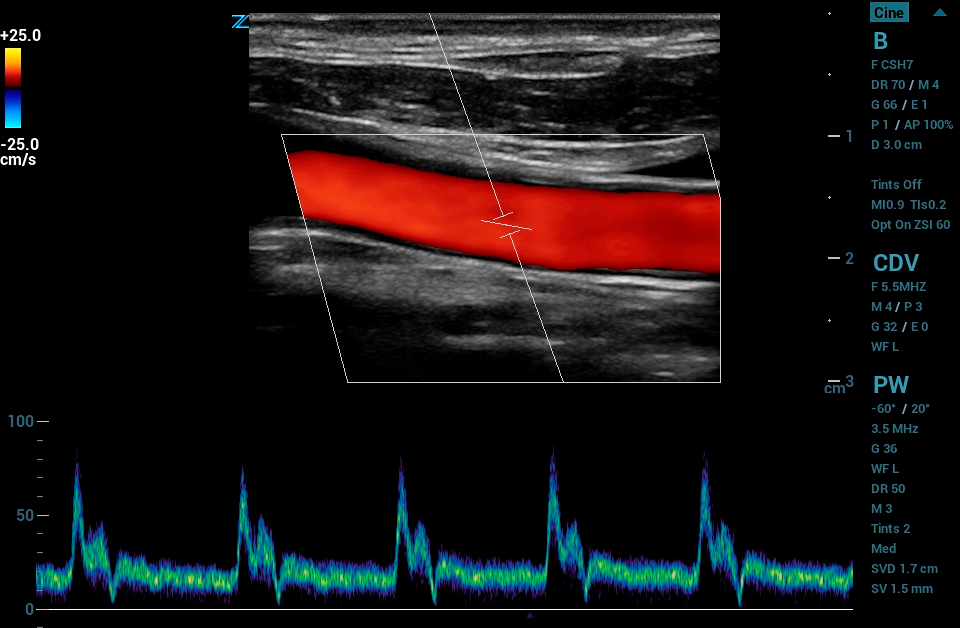

The ZS3 Ultrasound System Diamond Edition 2.0 is the ultimate imaging platform combining premium performance and mobility for today’s demanding ultrasound environments. Equipped with next generation ZONE Sonography® Technology+ (ZST+), the ZS3 System takes image clarity to new heights across a broad spectrum of body types from pediatric to bariatric. With every pixel in focus to imaging depths up to 40cm, the ZS3 System delivers unsurpassed image quality for the widest range of clinical applications.

Contrast Enhanced Ultrasound (CEUS), Mindray’s unique approach to contrast imaging, allows clinicians to obtain the information needed with a lower dose of the contrast agent. CEUS is now available on all imaging transducers (1-20MHz).